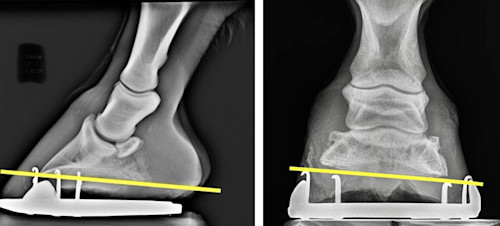

Most x-ray exams can be done at the barn and without sedation. The most common use of radiography is to image the legs, hooves, back, and neck, often in cases involving lameness or injury. Here are some examples of when x-ray may be used:

- X-rays of the feet could help your farrier with trimming and shoeing for optimal foot balance (Fig. 2).